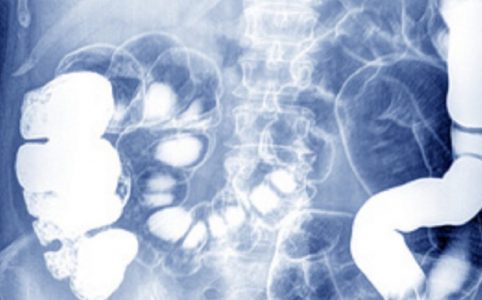

Hinweise, die an eine erbliche Veranlagung denken lassen, sind erstens Gicht in der Familienanamnese und zweitens der Abgang eines Uratsteins (Harnsäuresteins) mit dem Urin. Der Harnsäurespiegel des Serums sollte vom Hausarzt bei jedem Patienten bestimmt werden, der einen solchen Stein ausscheidet. Auch die Untersuchung des Gelenkwassers kann zu hohe Harnsäurewerte offenbaren. Immer wieder auftretende Anfälle von akuten Gelenkschmerzen mit symptomfreien Intervallen bei Patienten, denen sonst nichts fehlt, sind sehr verdächtig.